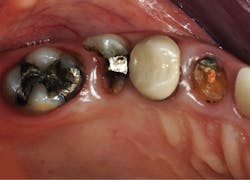

Use the following technique to remove deep caries for indirect restorations, such as crowns and onlays (figures 2–4):

Figure 2: This patient requires significant treatment. The second premolar was extracted, and the other three teeth received caries excavation and treatment as described in this article.